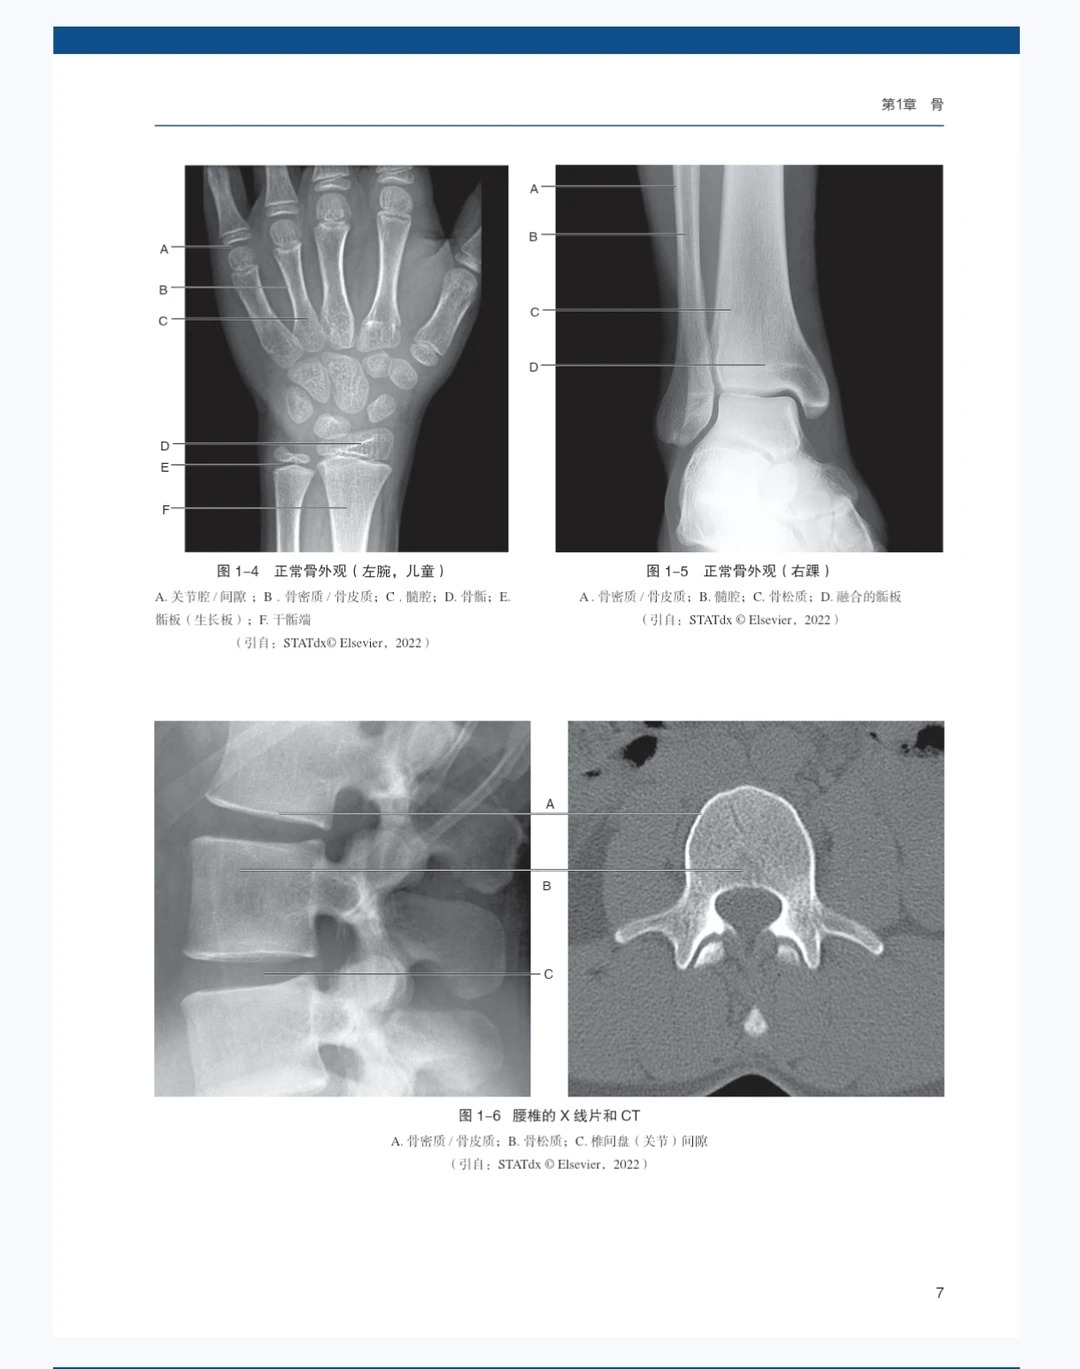

2. 图文超清,直观易懂 配备海量高清影像图+精美示意图+病例图,图文结合、看图说话,清晰呈现骨关节解剖结构、病变特征,细微病变也能精准识别,理解起来直观易懂,彻底解决“看图懵”的痛点,提升读片与学习效率。